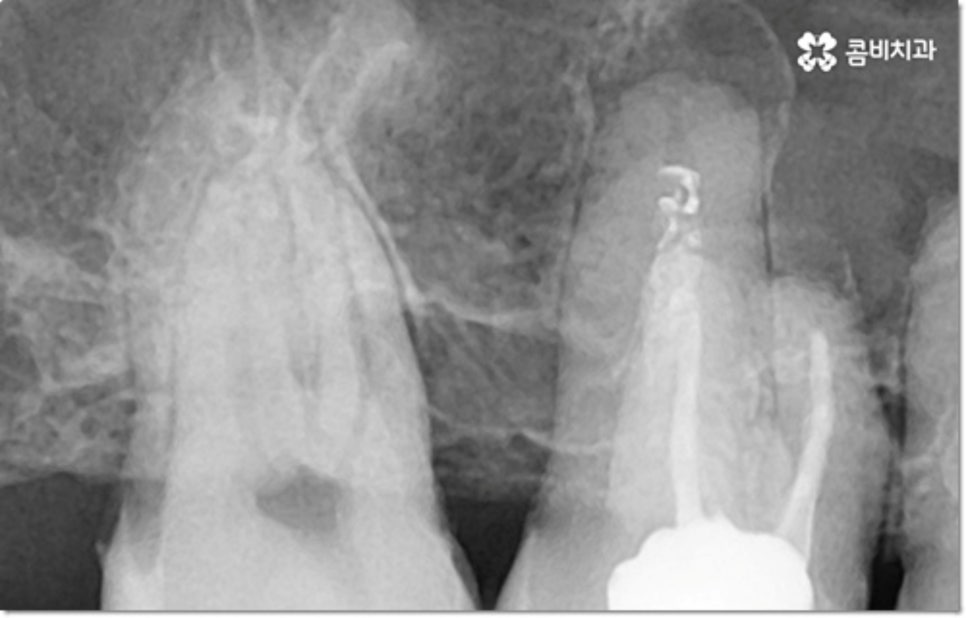

게다가 이러한 습관을 가지고 있으면 다른 정상 치아 역시 뿌리가 흡수되면서 짧아지는 치근 흡수가 일어날 수도 있습니다. 보통 치근 흡수는 교정 치료를 받을 때 간혹 너무 무리한 힘을 받은 치아에 부작용으로 나타나는 경우가 대부분이지만 교정과 상관없이 유전적인 질환 (갑상선기능항진증이나 파제트병 등)으로 인한 경우도 있고, 심각한 충격을 받은 치아 또는 매복치의 영향을 받은 인접 치아에 나타나는 경우도 있으며 말씀드린 것과 같은 구강악습관으로 인해 발생할 수도 있어요.

물론 갑자기 치아가 쑥 빠지거나 하는 것이 아니라 사진에서 볼 수 있듯이 치아 뿌리 끝부분이 둥글어지면서 짧아지는 정도이긴 하지만 아무래도 흔들림, 이시림 등의 불편함을 초래하고 치아와 잇몸을 약해지게 만들며 구강 건강 전체에 좋지 않은 영향을 줄 수 있으니 장기적으로 봤을 때도 이러한 습관은 바꾸시는 게 좋을 거예요.